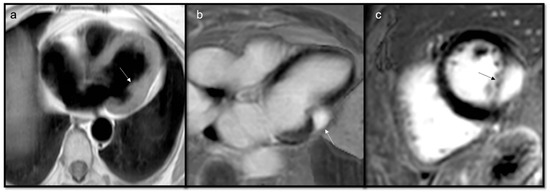

- Trombi due to their avascular nature appear non-enhanced.

- Organized thrombi may show peripheral enhancement on LGE images, owing to their fibrous content.